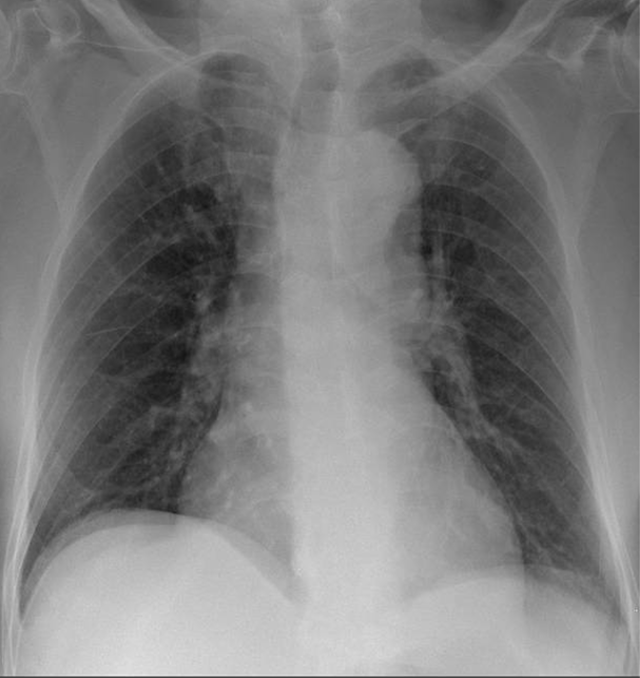

Hãy phân tích tình huống Nam 83 tuổi

1-Bất thường ảnh giả vòm hoành hai bên (artifact)